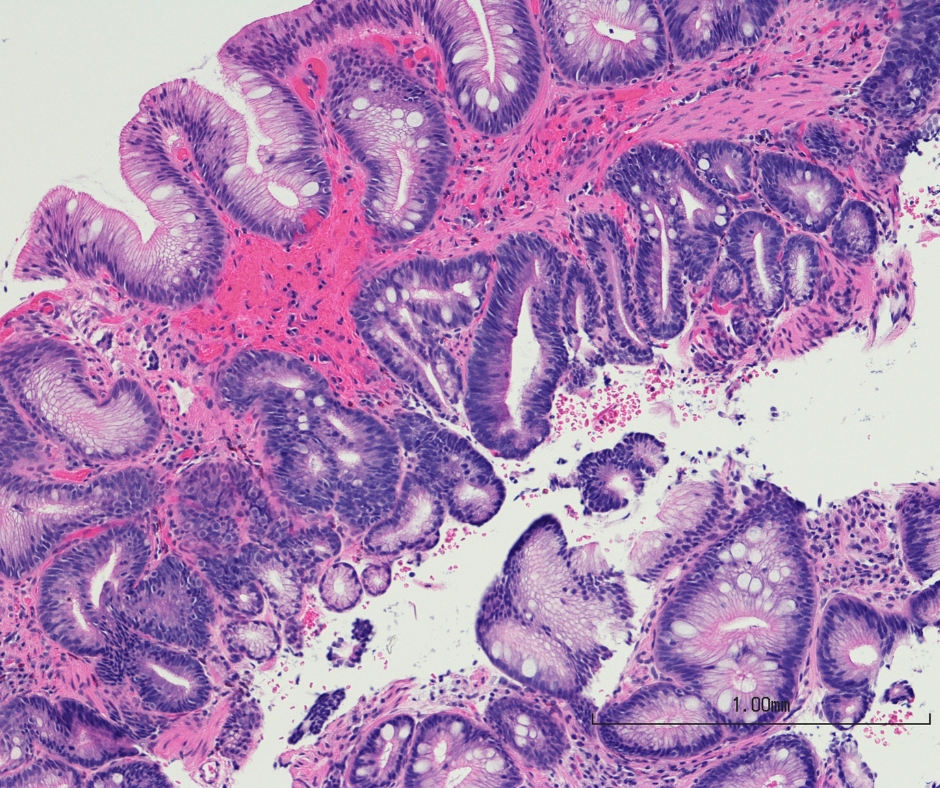

內視鏡黏膜下剝離術(Endoscopic Submucosal Dissection, ESD)是一種先進的微創內視鏡技術,廣泛應用於早期消化道病變的治療,如食道癌、胃癌、大腸直腸癌及癌前病變(如腸化生或大型瘜肉)。

腸化生是指胃黏膜細胞轉變為類似腸道細胞的情況,通常與慢性胃炎或幽門螺旋菌感染相關,增加胃癌風險。胃鏡檢查是診斷腸化生的主要方法,可直接觀察胃黏膜並配合活組織檢查,準確確認病變,為早期發現及預防胃癌提供重要依據。以下將詳細介紹胃鏡在腸化生診斷中的作用及其他輔助的檢查方法。

腸化生是一種常見的胃黏膜病理改變,與慢性胃部疾病及胃癌風險密切相關,它通常在長期炎症刺激下發生。了解腸化生的成因與風險因素,有助及早採取預防與治療措施,保障胃部健康。以下將詳細解析腸化生的定義及其成因,並提供相關的健康建議。